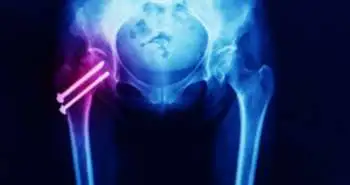

Чрескожная крестцово-подвздошная винтовая фиксация способствует облегчению боли, улучшению способности передвигаться и сокращению времени до выписки

J. Brock Walker и коллеги объяснили роль чрескожной крестцово-подвздошной винтовой фиксации в улучшении способности передвигаться, снижении интенсивности боли, снижении продолжительности госпитализации и времени до выписки при остеопоротических переломах крестца.

J. Brock Walker и коллеги объяснили роль чрескожной крестцово-подвздошной винтовой фиксации в улучшении способности передвигаться, снижении интенсивности боли, снижении продолжительности госпитализации и времени до выписки при остеопоротических переломах крестца. Данный метод фиксации при травмах заднего полукольца таза приобрел популярность в середине и конце 1990-х годов. В наши дни его применяют для лечения переломов крестца.

Для участия в исследовании были ретроспективно выбраны пожилые пациенты, перенесшие перелом крестца в период с августа 2015 г. по август 2017 г. (n = 41). Среди них 25 получили консервативное лечение, а 16 прошли процедуру чрескожной крестцово-подвздошной винтовой фиксации. В качестве клинически значимых исходов в рамках данного анализа рассматривали способность передвигаться, продолжительность госпитализации, интенсивность боли и время до выписки.

В группе хирургического лечения наблюдалось снижение интенсивности боли (3,9 балла) по ВАШ по сравнению с группой консервативной терапии (0,6 балла, p < 0,001). У 100 % пациентов в группе хирургического лечения сохранилась способность передвигаться по сравнению с 72 % пациентов в группе нехирургического лечения (p = 0,03). В группе хирургического лечения также наблюдалась способность передвигаться на большее расстояние при выписке (в среднем 95 и 35 футов соответственно). Продолжительность госпитализации в обеих группах была практически одинаковой (хирургическое лечение — 3,6 дня; консервативное лечение — 4,2 дня). В группе хирургического лечения в исследуемый период выписались 75 % пациентов, а в группе консервативного лечения — 20 % пациентов. Осложнения во время операции не наблюдались. В целом чрескожная крестцово-подвздошная винтовая фиксация способствует решению проблем, связанных с остеопоротическими переломами крестца. Тем не менее, для оценки преимуществ данного метода с точки зрения исходов в среднесрочной и долгосрочной перспективе требуется проведение дополнительных исследований.